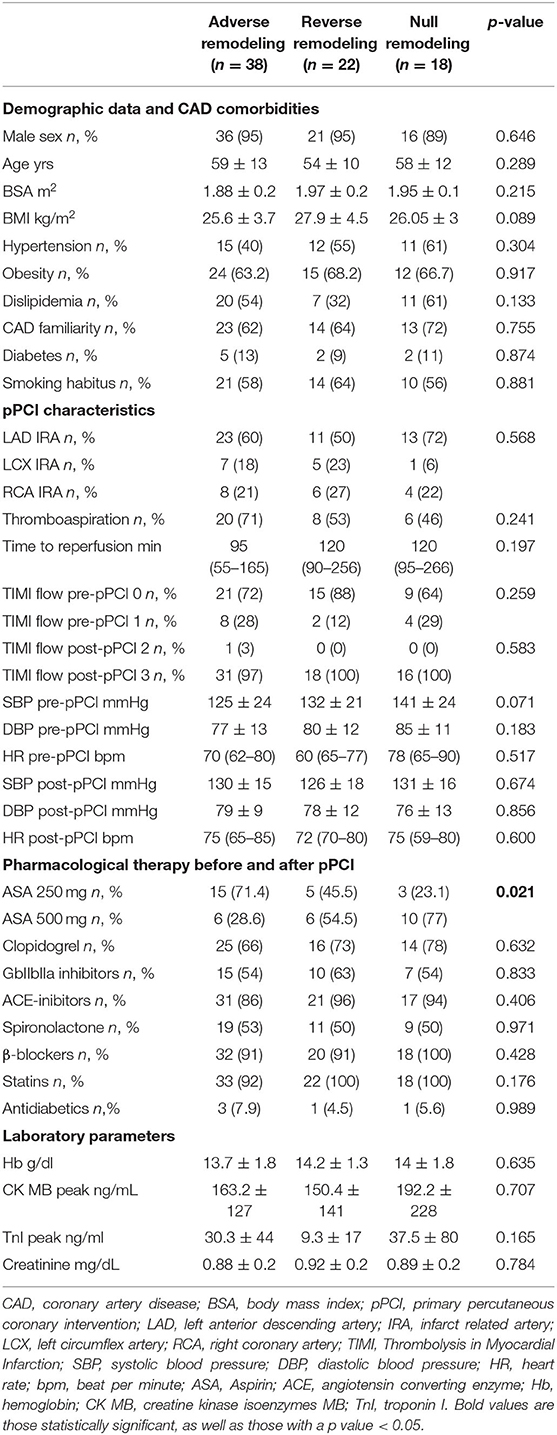

From 2010 to 2019, a total of 1,285 STEMI patients underwent pPCI in Policlinico Umberto I Hospital, of which ~15% had CMR performed and 78 were recruited as reported in the flow chart (Figure 1). According to our internal procedures, when allowed by the clinical condition of the patient, the availability of the scanner/staff, and in the absence of contraindications, CMR was performed in reperfused STEMI patients for the assessment of post-infarction myocardial injury during the acute phase and to detect complications at short and long term follow up. Among the study population of enrolled STEMI patients, 38 (49%) showed adverse, 22 (28%) reverse, and 18 (23%) null LV remodeling, assessed by paired CMR exams (baseline and FU-CMR). Demographic, clinical, angiographic, and pharmacological characteristics of the STEMI population according to the three groups are illustrated in Table 1. No differences in demographic data, cardiovascular risk factors, angiographic presentation, or laboratory findings were found. Agreement in strain measurements was excellent with ICC between 0.922 and 0.943 (p < 0.001, Supplementary Material) and p > 0.43 (range 0.43–0.85) at Wilcoxon's test. Regarding pharmacological therapy, no differences were noted about beta-blocker, antidiabetics, statins, ACE-inhibitors, spironolactone, GbIIb-IIIa inhibitors, and clopidogrel use among the three LV remodeling categories, except for the pre-pPCI ASA administration. At the first CMR exam, patients with LV adverse remodeling showed higher AAR, IS, and MVO, if compared to the other two groups (Table 2). Meanwhile, at FU-CMR, the adverse remodeling group had lower LVEF, greater IS extent, and lower LV-RI. At CMR strain analysis, significantly worse GCS and GLS values at baseline and FU-CMRs in the adverse LV remodeling group, compared to the sum of the other two groups, were found (Figure 2, Table 2). After adjusting for age, sex, BMI by ANCOVA analysis, the only CMR derived parameters that reported a different statistical significance if compared with ANOVA analysis, according to the three remodeling groups, were baseline AAR, baseline MVO, FU IS, baseline GRS, and baseline GLS.

Table 1. Demographic, clinical, pharmacological, and angiographic characteristics according to LV remodeling groups.